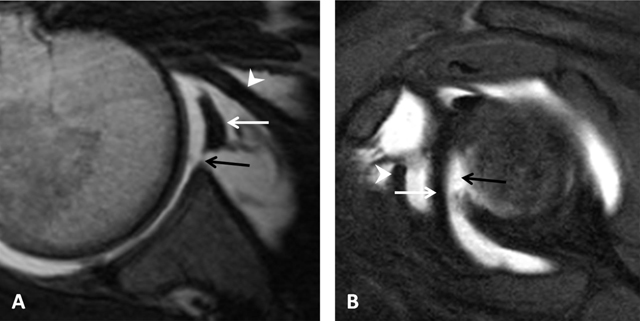

Figure 23

Inferior glenohumeral ligament. (A) Sagittal oblique PD-weighted MRA depicts the inferior glenohumeral ligament (thick arrows, A) with a high labral attachment (arrowhead, A). Coracohumeral ligament (thin arrow, A). (B) Sagittal oblique PD-weighted MRA shows the anterior band of the inferior glenohumeral ligament (white arrows, B) and the posterior band of this ligament (black arrows, B).